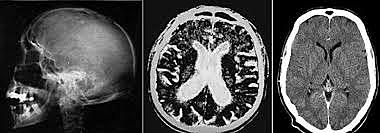

• Primera tomografía

Primera tomografía

El uso de la TC en la radiología se ha desarrollado mucho desde

la primera tomografía de un paciente .

• Sir Godfrey Hounsfield y el  Dr. Jamie Ambrose

Sir Godfrey Hounsfield y el Dr. Jamie Ambrose

presentaron un artículo titulado “Computerised axial tomography (the new means of demonstrating some of the soft tissue structures of the brain without the use of contrast media)” [Tomografía axial computarizada (el nuevo medio para demostrar algunas de las estructuras del tejido fino del cerebro sin el uso de medios de contraste)] en el 32.º congreso anual del Instituto Británico de Radiología.